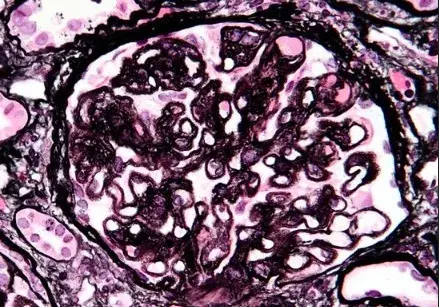

A biópsia renal revelou GN crescêntica necrotizante difusa sem hipercelularidade endocapilar. Alguns raros glomérulos continham células gigantes multinucleadas.

A avaliação da microscopia de luz pode ajudar na diferenciação de casos de **GN por anti-MBG** de casos **GN-ANCA**, já que na GN anti-MBG não observamos hipercelularidade endocapilar e pode ser identificado a presença de células gigantes multinucleadas, estas células gigantes multinucleadas resultam a natureza explosiva e a rápida destruição dos glomérulos observadas em anti-MBG

Desta forma, a presença de lesões crescentes temporalmente semelhantes e células gigantes multinucleadas na microscopia de luz (MO) pode ajudar no diagnóstico precoce.